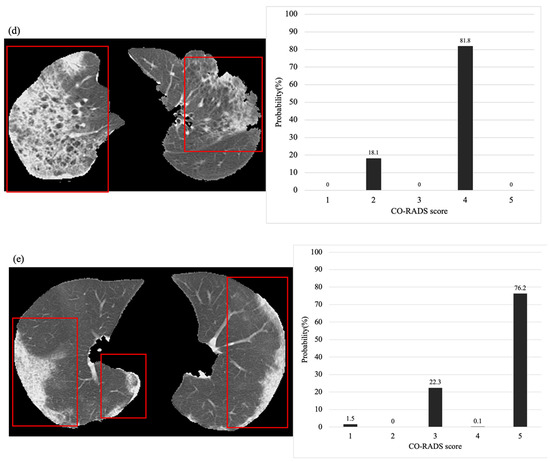

Table 2 summarizes the patient characteristics for the training and test datasets. Figure 4 shows the CT images of three representative cases and the probability of obtaining different CO-RADS scores based on the deep-learning classification model. There were no significant differences in the distribution of age between the training and test data (p = 0.06), male-to-female ratio among patients (p = 0.07), and CO-RADS score distribution (p = 0.12).

Figure 4.

Representative output from the classification model. (a) The CT image shows no abnormal density in both lungs. The classification model presented a 100% probability of a CO-RADS score of 1. (b) CT imaging shows multiple centrilobular nodules in both lungs. The classification model presented an approximately 99% probability of obtaining a CO-RADS score of 2. (c) The CT images show unilateral nonspecific ground-glass opacity in the dorsal aspect of the left lung. The classification model presented an approximately 70% probability of obtaining a CO-RADS score of 3. Although a score of 3 was determined, the possibility of 1 or 5 was also suggested. (d) CT imaging shows bilateral subpleural predominant ground-glass opacity and consolidation and strong emphysematous changes in the background. In classification models, a CO-RADS score of 4 is most likely. (e) The CT image shows crazy-paving-like ground-glass opacity in the bilateral subpleural areas. The classification model also presents the highest possibility of a CO-RADS score of 5.